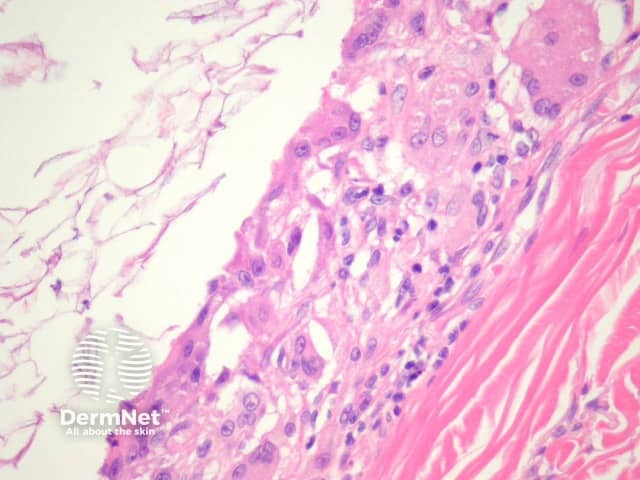

Sections of an epidermoid cyst show a cystic structure occupying at least the upper dermis but larger lesions may grow to involve the entire dermis (figure 1). They are usually unilocular but are rarely multilocular. The lining of the cyst is composed of an epithelium which is flattened and contains a granular layer of keratohyaline granules (figures 2, 3). The cyst lining is similar to the surface epithelium but lacks rete ridges which are seen in the overlying epidermis (figure 4, arrow).

Foci of rupture are common and the keratin exposed to the adjacent dermis elicits a neutrophilic and then granulomatous reaction (figures 5, 6).

Figure 3

Figure 4